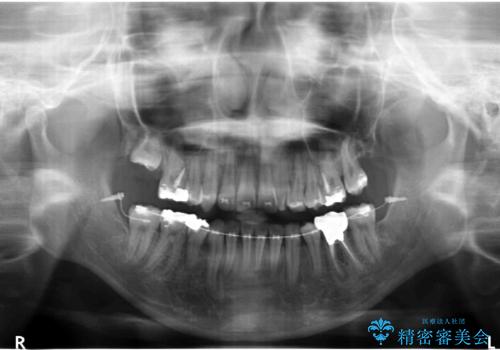

- 前歯のがたつきを主訴に来院されました。

小さいころ下の小臼歯を2本抜いたとのことでした。

上の歯を2本抜歯して矯正しています。

また、右上の7番(一番後ろの歯)の状態が悪く、根尖病変がありました。根の治療をする選択肢もありましたが、歯質も薄く、予算的にも治療が難しかったため、抜歯して親知らずを並べています。

左下6番(後ろから2番目の歯)も状態が悪かったため抜歯してブリッジにしています。

矯正治療をしたことで根の向きが治り、神経を取らずにブリッジにすることができました。